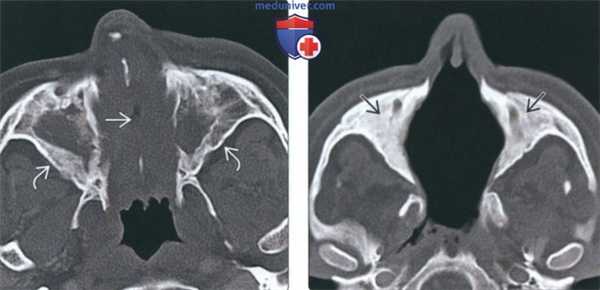

(Слева) На аксиальной КТ в костном окне полость носа полностью заполнена мягкими тканями, пневматизация обеих верхнечелюстных пазух тотально снижена. Определяется перфорация носовой перегородки утолщение и склероз стенок пазух - все изменения сопоставимы с ГПА.

(Справа) На аксиальной КТ в костном окне у пациента с поздней аадией ГПА определяется деструкция костных структур полости носа, в т.ч. носовой перегородки. Верхнечелюстные пазухи облитерированы вследствие утолщения костной ткани.

о Часто наблюдается перфорация носовой перегородки

о Точечные очаги деминерализации кости:

- По ходу перфорирующих артерий; признак васкулита

о Деструкция носовых раковин и наружной стенки полости носа (крючковидного отростка и внутренней стенки верхнечелюстной пазухи):

- Вначале разрушаются перегородка и раковины, затем обе верхнечелюстные пазухи, после чего-остальные пазухи